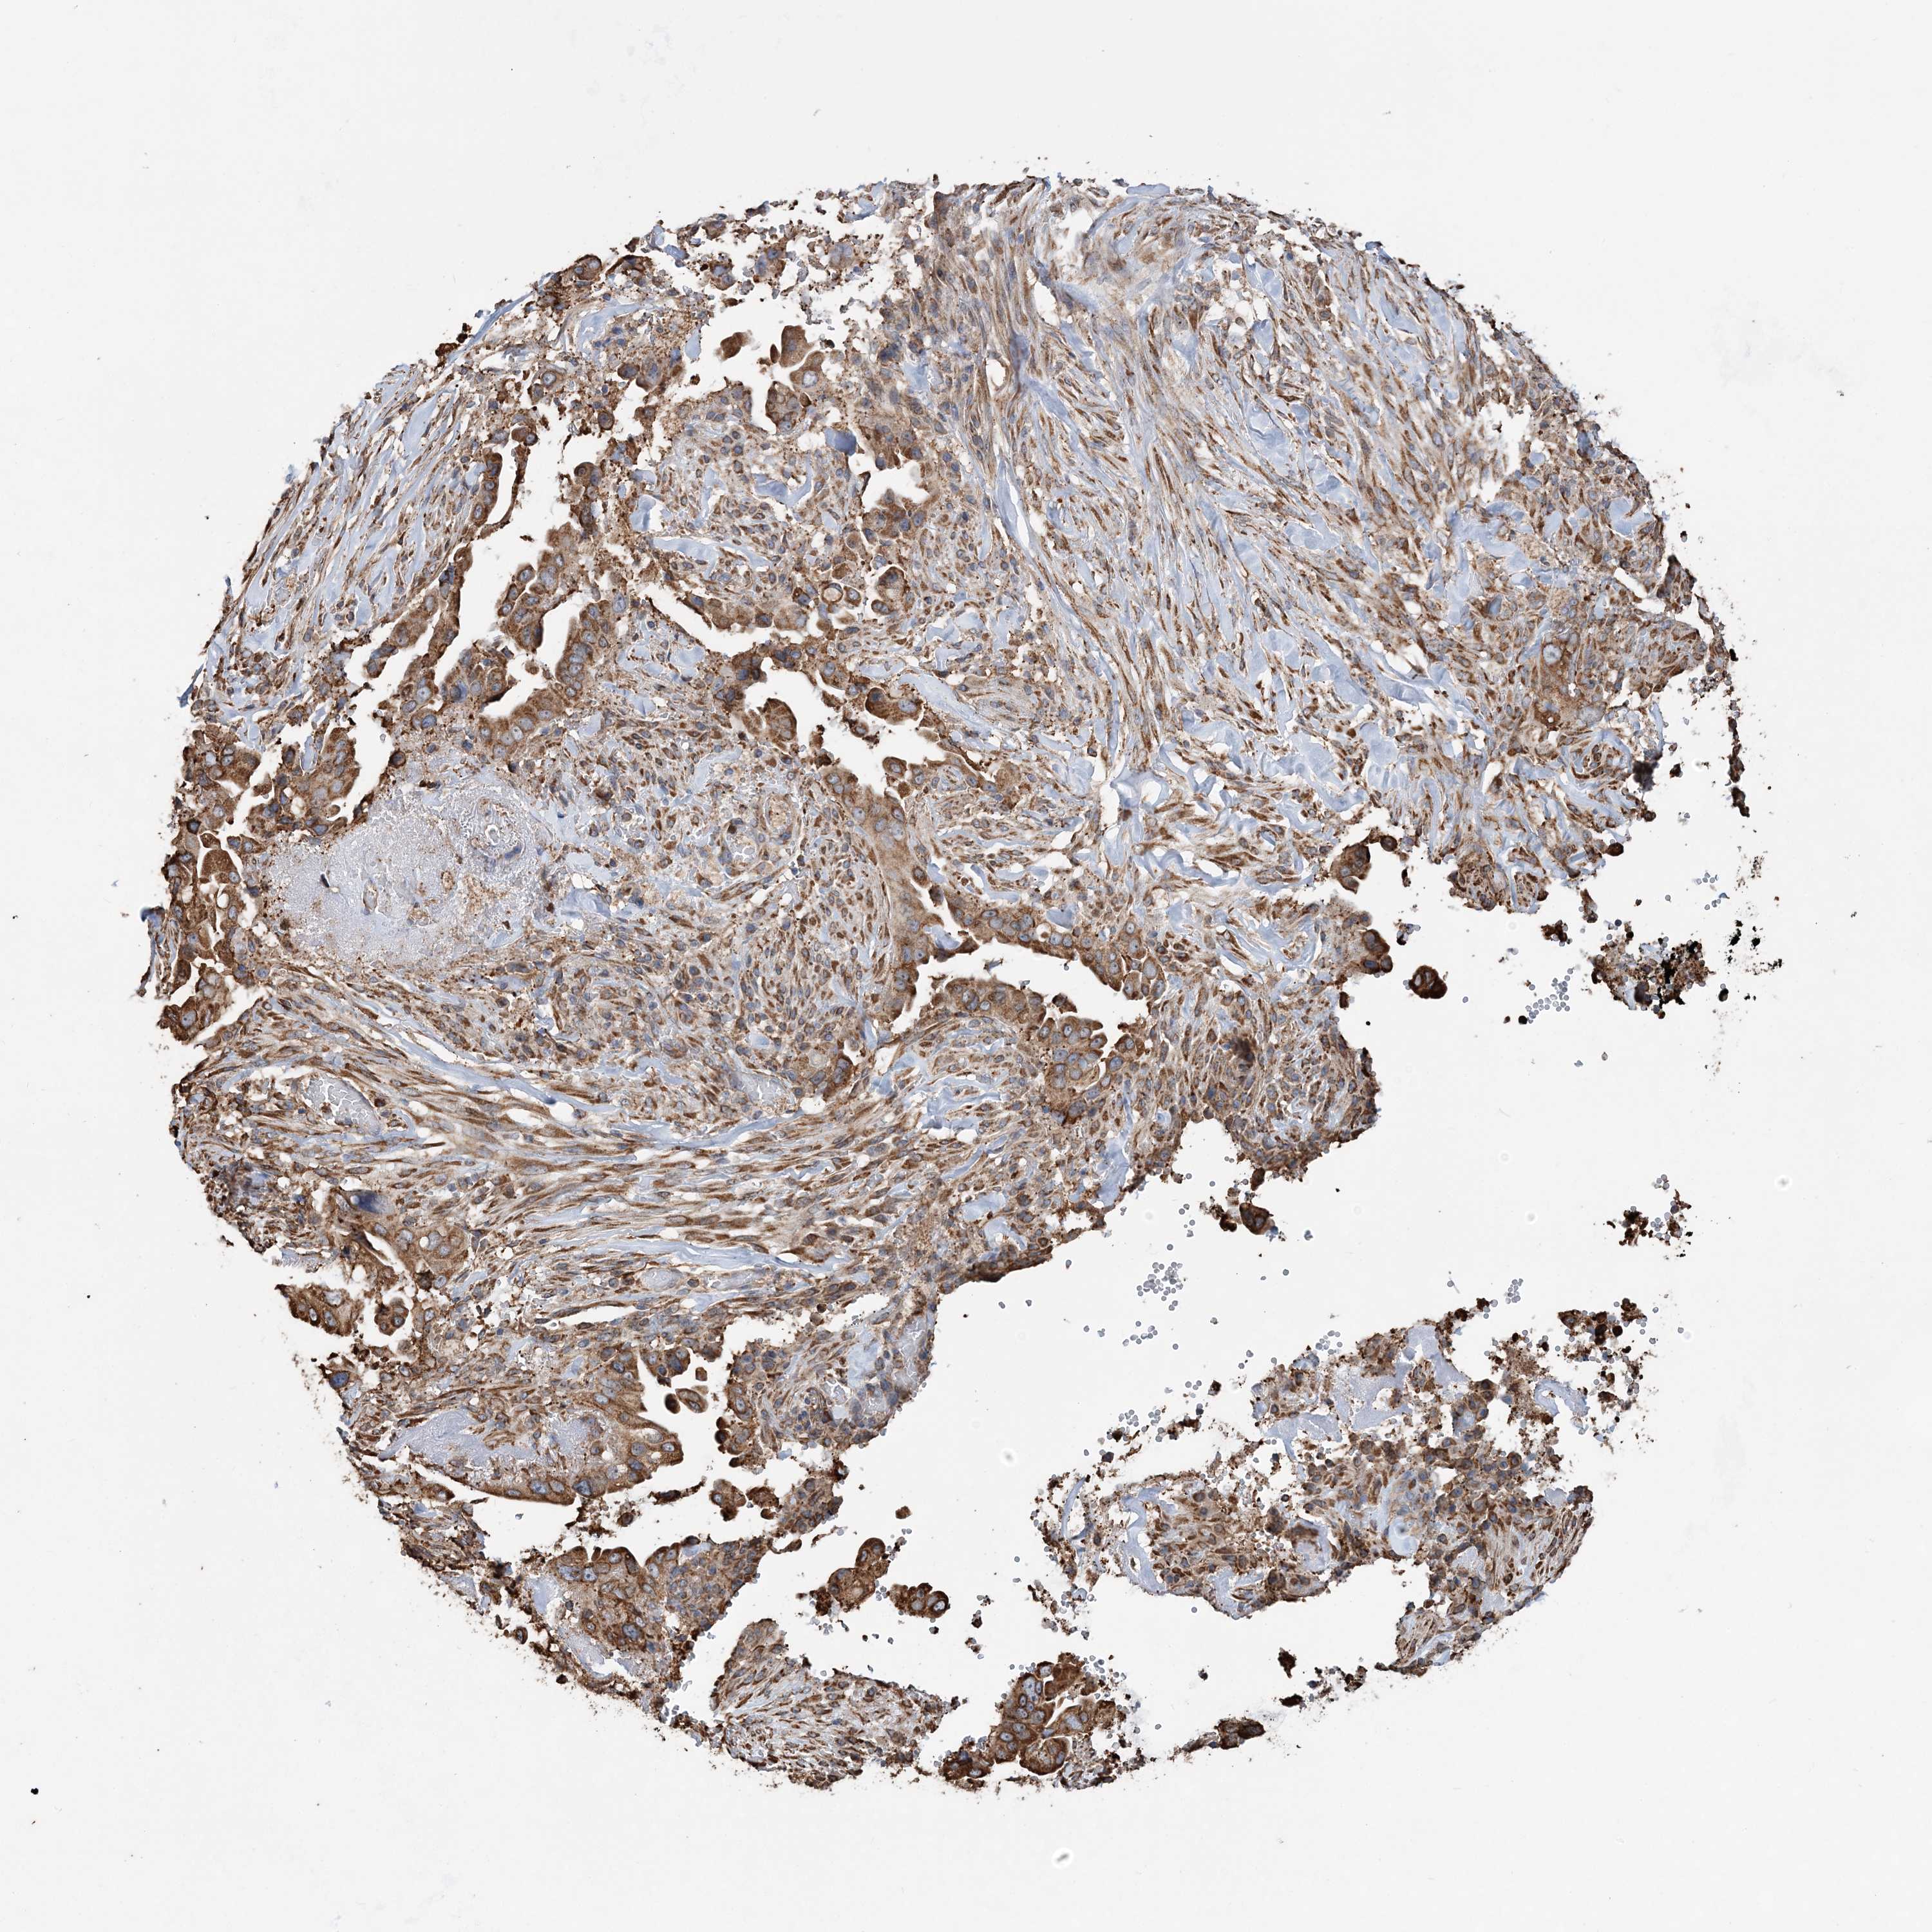

PANCREATIC CANCER - Protein expressioni

A mouse-over function shows sample information and annotation data. Click on an image to view it in a full screen mode. Samples can be filtered based on level of antibody staining by selecting one or several of the following categories: high, medium, low and not detected. The assay and annotation is described here.

Note that samples used for immunohistochemistry by the Human Protein Atlas do not correspond to samples in the TCGA dataset.

Antibody stainingi

Antibody staining in the annotated cell types in the current human tissue is reported as not detected, low, medium, or high, based on conventional immunohistochemistry profiling in selected tissues. This score is based on the combination of the staining intensity and fraction of stained cells.

Each image is clickable and will lead to virtual microscopy that enables deeper exploration of all samples and also displays staining intensity scores, fraction scores and subcellular localization as well as patient and tissue information for each sample.

Antibody HPA036389

Staining

High

Medium

Low

Not detected

Intensity

Strong

Moderate

Weak

Negative

Quantity

>75%

75%-25%

<25%

None

Location

Nuclear

Cytoplasmic/membranous

Cytoplasmic/membranous,nuclear

Adenocarcinoma, NOS